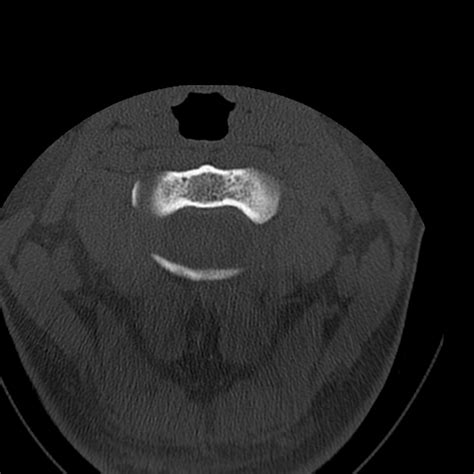

• Computed Tomography (CT) Scan: This is the gold standard for diagnosing occipital condyle fractures. CT scans provide detailed images of the bony structures and can help identify the location and extent of the fracture.

Occipital condyle fractures are classified based on their pattern and mechanism of injury. The most commonly used classification system is the Anderson and Montesano classification, which categorizes these fractures into three types:

Type III Avulsion fracture of the occipital condyle Altered rotational forces